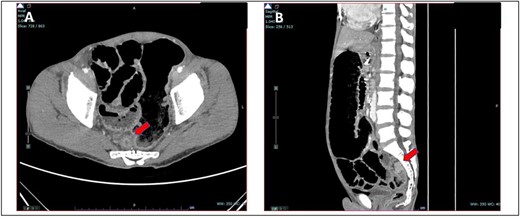

A 52-year-old Malay man, an active smoker, with underlying pulmonary hypertension secondary to atrial septal defect secundum with Eisenmenger syndrome and chronic lung disease. He had been experiencing symptoms of intestinal obstruction for a week. He had abdominal pain for 1 day, vomiting for 2 days, and unable to pass motion for the past 1 week. Patient was tachypnoeic with a respiratory rate of 35/min, a pulse rate of 116 bpm, and SPO2 of 90% under high-flow nasal cannula 50%/50 L. Abdominal radiograph showed dilated large bowel. Computed tomography abdomen and pelvis revealed short segment circumferential enhancing bowel wall thickening at rectosigmoid region causing intraluminal obstruction and presence of target sign at left lumbar region suggestive of jejunojejunal intussusception (Figs 2 and 3).

(A) Axial view and (B) sagittal view of computed tomography showed short segment circumferential enhancing bowel wall thickening at rectosigmoid region causing intraluminal obstruction (red arrow).